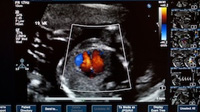

Diagnosing Pediatric Heart Failure

The doctor might also order tests such as: